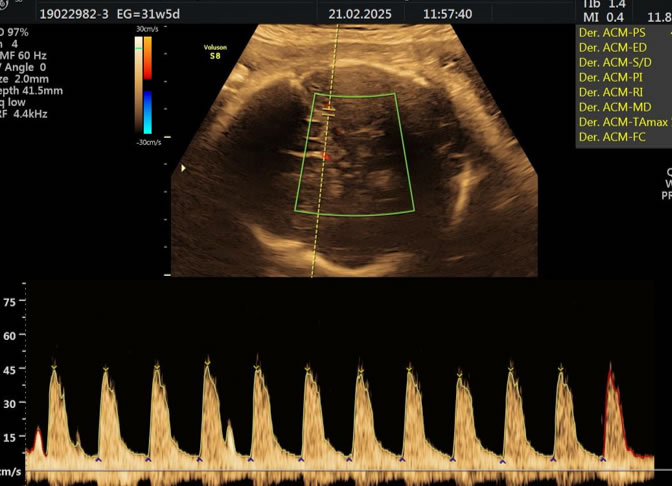

• Eco Doppler III Trimestre

Doppler Center